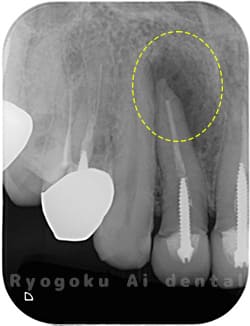

Case01

- 原因

- 慢性根尖性歯周炎

- 治療期間

- 1回(消毒・洗浄も含めると3回)

- 治療内容

- 歯根端切除術

- 治療費用

- ¥110,000

他院で抜歯と判断され、インプラント治療を提案された患者様です。被せ物を外さずに、歯の根尖部に外科的にアプローチし、病気の部分を除去しました。

<リスク・副作用>

外科手術のため、術後に出血、痛みや腫れ、違和感を伴います。口腔内の状態によっては適応できないことがあります。歯根端切除で治らなければ抜歯を検討しなくていけない場合もあります。